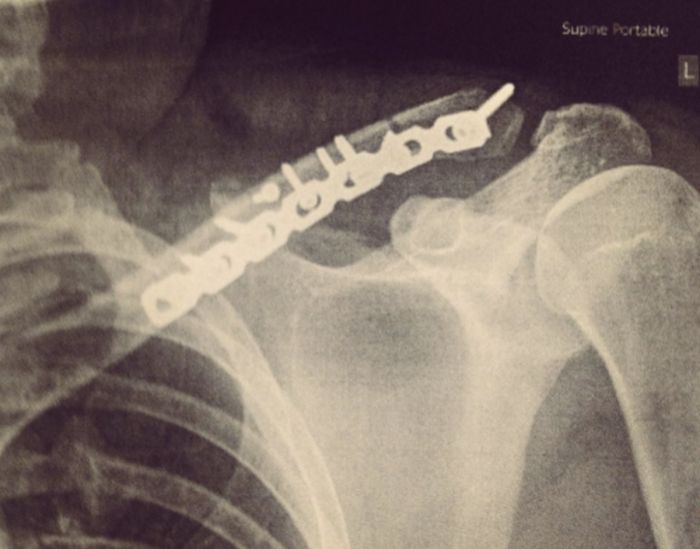

Парень решил сохранить на память металлическую пластину, которая фиксировала его ключицу в течение года после перелома, полученного в результате неудачного катания на лыжах. Извлеченный из тела металл послужил материалом для изготовления оригинального кольца с необычным дизайном, которое теперь украшает безымянный палец любителя лыжного спорта.